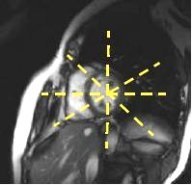

Figure 8. Short axis prescriptionFigure 9. Long axis radial prescription